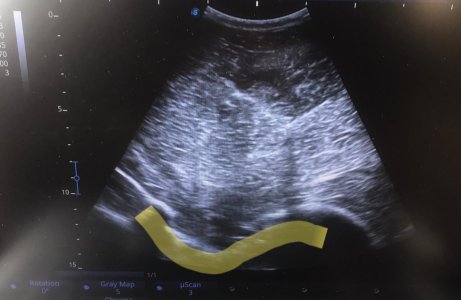

I don’t have undoctored images of this but this is the most random equine diagnostic image I’ve got I think. Anyone like to guess the imaging modality and what the arrow is pointing at?

Yup. Where the yellow line is it should be a natural curve. Instead there is a step where the pelvis has broken and displaced. It's really not an obvious one unless you know you were looking at a pelvis - which hopefully none of you lot ever have to!

We're at a disadvantage here because if you take an xray or do an ultrasound, presumably you know which part of the body you're aiming at. :D